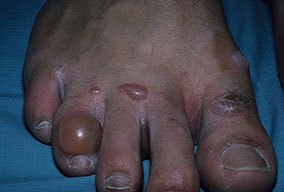

The spectrum of foot infections in diabetes ranges from simple superficial cellulitis to chronic osteomyelitis. Infections in patients with diabetes are difficult to treat because these patients have impaired microvascular circulation, which limits the access of phagocytic cells to the infected area and results in a poor concentration of antibiotics in the infected tissues. For this reason, cellulitis is the most easily treatable and reversible form of foot infections in patients with diabetes. Deep skin and soft tissue infections are also usually curable, but they can be life threatening and result in substantial long-term morbidity.

Patients with diabetes also can have a combined infection involving bone and soft tissue called fetid foot. This extensive, chronic soft tissue and bone infection causes a foul exudate and usually requires extensive surgical debridement and/or amputation.

Individuals with diabetes may also have peripheral vascular disease that involves the large vessels, in addition to microvascular and capillary disease that results in peripheral vascular disease with gangrene. Dry gangrene is usually managed with expectant care, and gross infection is usually not present. Wet gangrene usually has an infectious component and requires surgical debridement and/or antimicrobial therapy to control the infection.

Except for chronic osteomyelitis, infections in patients with diabetes are caused by the same microorganisms that can infect the extremities of those without diabetes. Gas gangrene is conspicuous because of its low incidence in patients with diabetes, but deep skin and soft tissue infections, which are due to gas-producing organisms, frequently occur in patients with diabetes. In general, people with diabetes have infections that are more severe and take longer to cure than equivalent infections in other people.